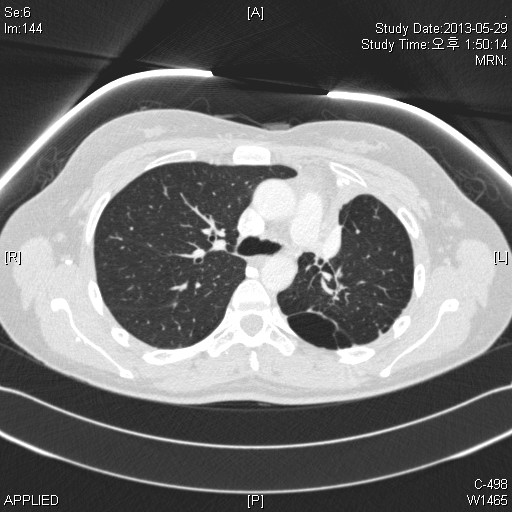

´ä: LUL atelectasis

chest PA¿¡¼­ Lt heart borderÀÇ À½¿µÀÌ Èå·ÁÁö°í aortic knobÁÖº¯À¸·Î ³´¸ð¾çÀÇ ÀúÀ½¿µÀÌ °üÂû.

chest Lat¿¡¼­ ÁÂÇÏ¿±ÀÌ ÆØÃ¢µÇ¸ç major fissure°¡ ¾ÕÀ¸·Î ´ç°ÜÁø ¸ð½ÀÀÌ °üÂûµÊ.

°­»ç¿Ü·¡ ³»¿øÈ¯ÀÚ·Î LUL atelectasis¸¦ CXR¿¡¼­ ¾Ë ¼ö ÀÖ´Â case·Î ¿Ã·ÁºÃ½À´Ï´Ù.

ÀÌȯÀÚ´Â endoTBc sequalle·Î »ý±ä°ÍÀ¸·Î º¸À̰í ÇÑ ÄÆ»ÓÀÌÁö¸¸ CT Âü°íÇϽöó°í ¿Ã¸³´Ï´Ù.